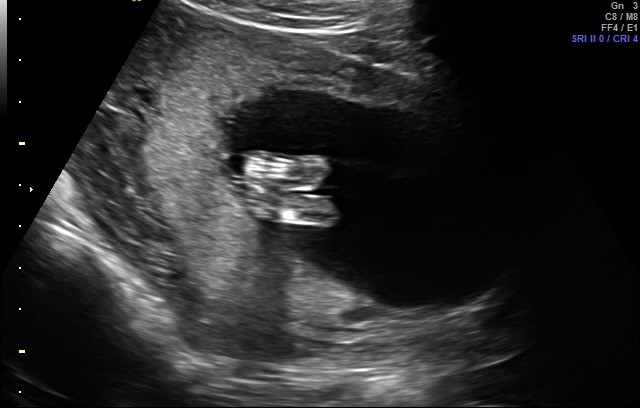

I was told a boy by this ultrasound photo, but i am having a hard time understanding the picture. Can someone help? I was sure I was having a girl, too, and this isn’t helping my confusion! https://uploads.tapatalk-cdn.com/201...d73731cca5.jpg